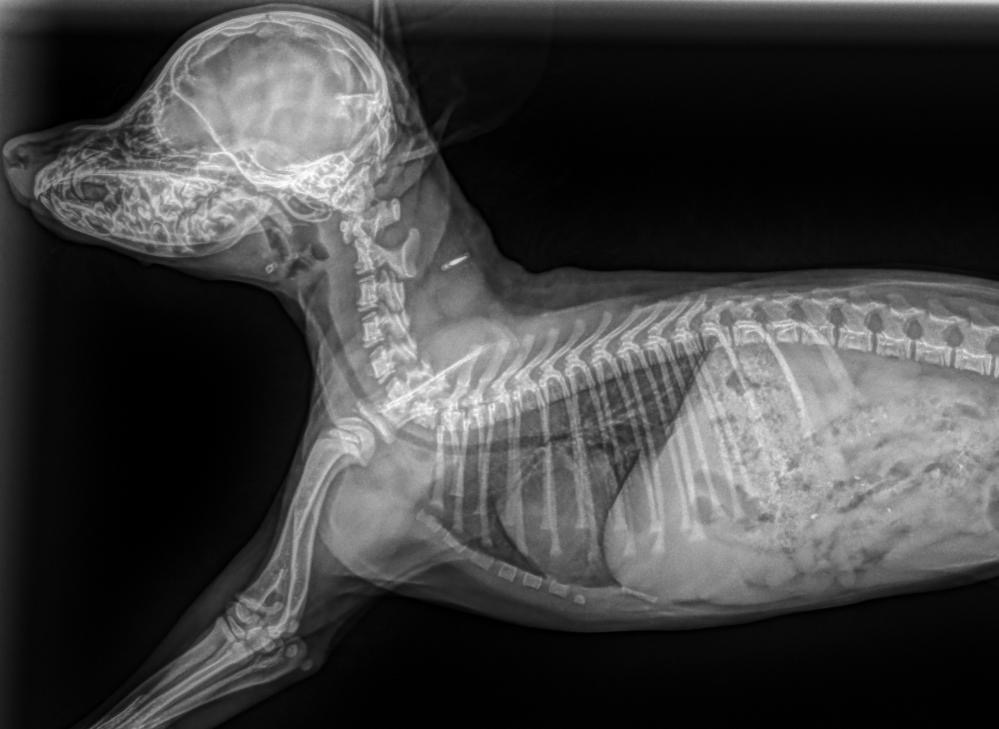

My heart is breaking. Sweet 8-week-old toy poodle, Matilda, broke her neck in two places. She’s just a baby… So full of love and life & now she can’t move her little legs. But since she is so young the specialist thinks there is still a chance.